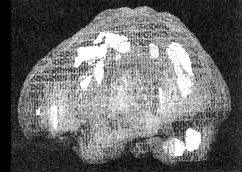

Мозг Линды. Результаты сканирования SPECT

Трехмерное изображение — активный мозг, вид снизу.

До лечения: обратите внимание на выраженное усиление активности в поясной системе, в базальных ганглиях и в лимбической системе.

После лечение зверобоем. Активность в поясной системе, в базальных ганглиях и в лимбической системе нормализовалась.